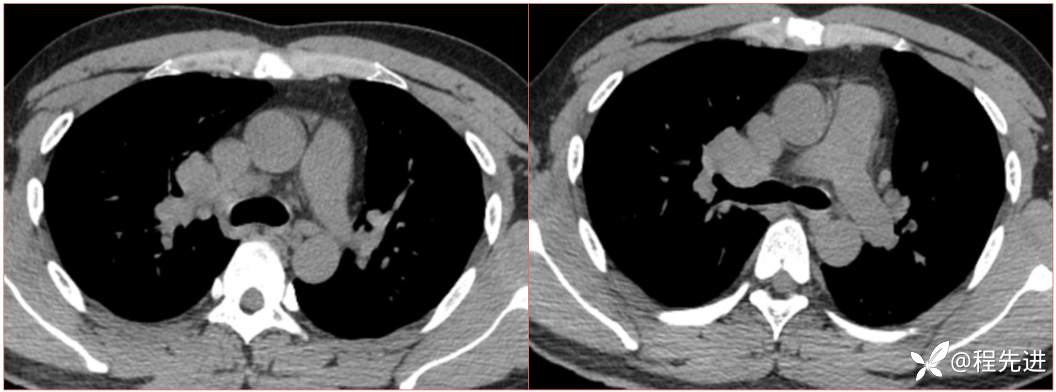

2023国庆特别精彩病例(一)|阵发性刺激性咳嗽,咳少量白色粘液痰1周|结果已公布

患者年龄:34岁

简要病史:患者一周前无明显诱因出现阵发性刺激性咳嗽,咳少量白色粘液痰,咳嗽无明显昼夜节律性,无发热、畏冷、寒战,无头痛、胸闷、胸痛,自行服药后 (具体不详) 症状无缓解,3天前外院胸片检查示右上病变

辅助检查:肺肿瘤标志物:神经元特异性烯醇化酶(NSE):35.72ng/ml(参考值0-16.3);非小细胞肺癌相关抗原211、胚抗原糖类抗原125、铁蛋白、鳞状细胞癌抗原未见异常